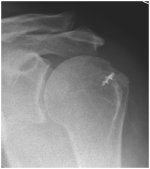

Cuff arthropathy